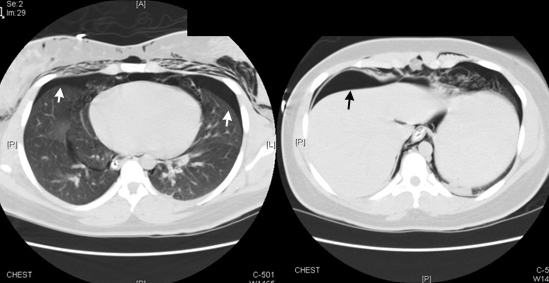

Lower cuts confirmed bilateral pneumothoraces and a pneumoperitoneum.